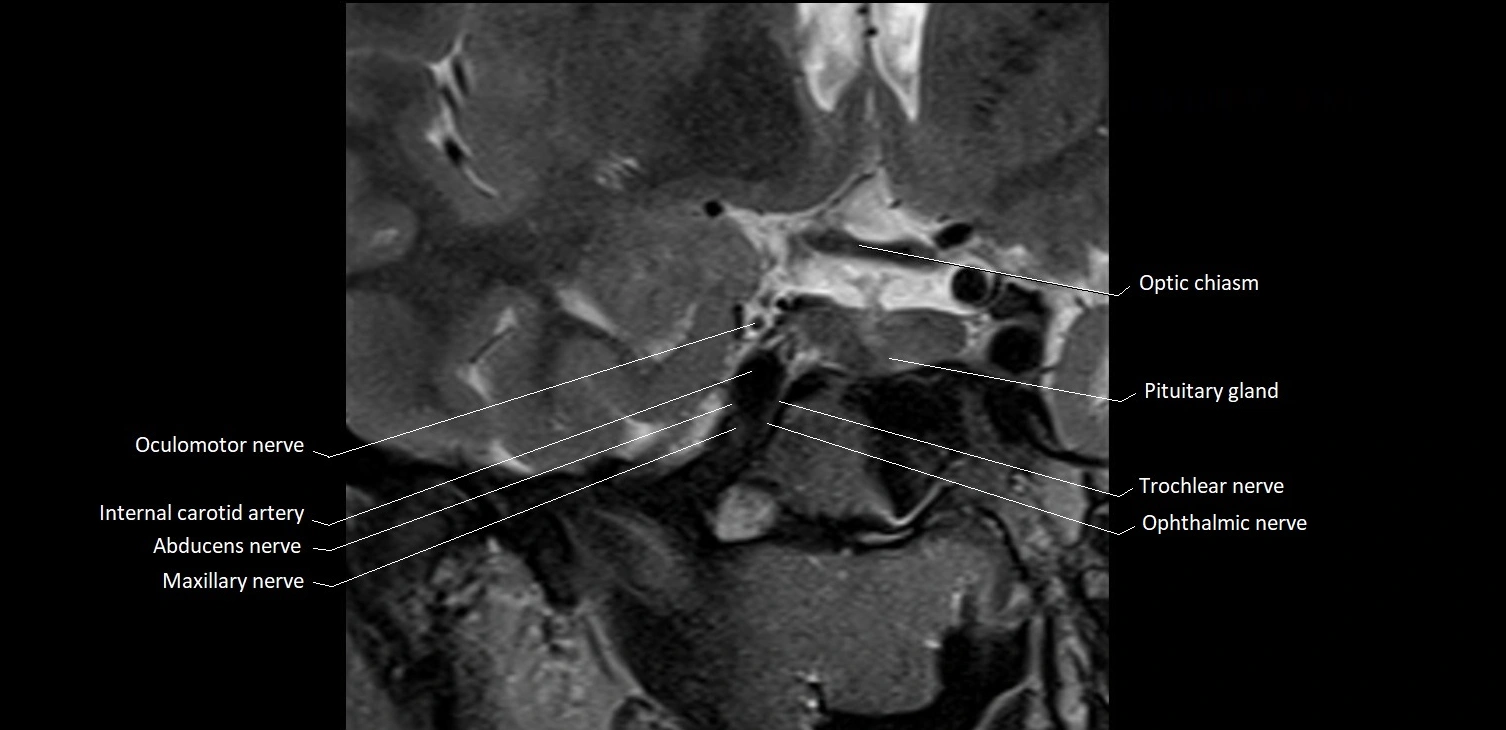

- Abducens nerve (Cranial nerve VI)

- Maxillary nerve

- Oculomotor Nerve (Cranial Nerve III)

- Trochlear nerve (Cranial nerve IV)

The Abducens nerve (Cranial nerve VI) is a purely motor cranial nerve responsible for innervating the lateral rectus muscle of the eye, which is crucial for lateral movement (abduction) of the eyeball. It arises from the abducens nucleus in the dorsal pons, emerges at the pontomedullary junction, and travels a long intracranial course before entering the orbit via the superior orbital fissure. Because of its long path and proximity to the clivus, it is particularly susceptible to injury from increased intracranial pressure or trauma.

MRI Appearance

The abducens nerve is a small, thin, linear structure

Best visualized on high-resolution T2-weighted 3D MRI sequences (e.g., FIESTA or CISS)

Seen as a hypointense (dark) line running from the brainstem at the pontomedullary junction, traversing the prepontine cistern, and entering Dorello’s canal under the petrosphenoidal ligament, then into the cavernous sinus, and finally the orbit

May be challenging to visualize in standard MRI due to its small size

Pathology may be inferred by absence, displacement, or enhancement of the nerve